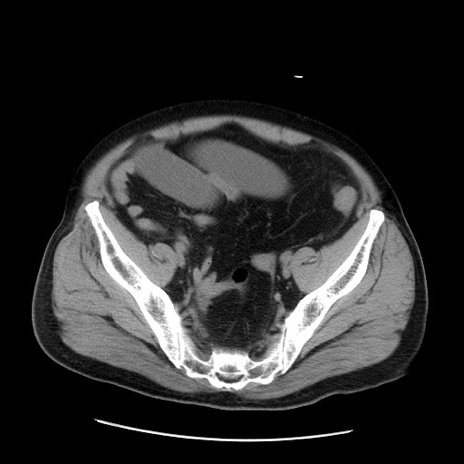

症例20(横断像)

【症例】 60歳代男性

【主訴】 腹部膨満、嘔吐

【現病歴】5日前頃より倦怠感を認め食事量減少し4日前の朝嘔吐、食事摂取困難となった。 3日前近医受診し点滴施行され整腸剤などを処方された。 当日他院を受診し、腹部膨満著明、炎症反応の上昇(CRP10.8、WBC11200)あり、紹介受診となる。

【身体所見】 意識JCS1 受け答えがはっきりしないBP 111/57mHg、 P 67bpm、、BT35.2°C、SpO2 97%(RA)、 腹部:膨隆、打診で鼓音あり、全体的に圧痛有り、腸蠕動音(-)、反跳痛ははっきりせず。

【データ】WBC 11400、CRP 14.20